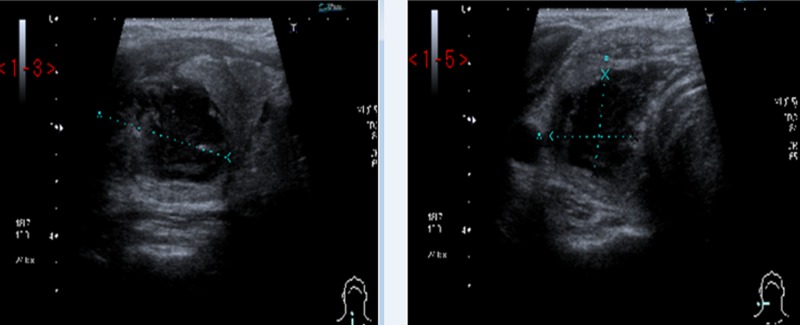

Figure 4.

Ultrasound scan of the neck showing 21 mm×18 mm×31 mm well-defined hypoechoic area within the right-sided strap muscles indenting the superior border of the right lobe of the thyroid gland.

The soft tissue neck X-ray (figure 3) did not show any retained radio-opaque foreign body. The ultrasound scan (USS) of his neck revealed a 21 mm×18 mm×31 mm well-defined hypoechoic area within the right-sided strap muscles indenting the superior border of the right lobe of the thyroid gland. Overall, the appearances were consistent with a resolving infection or haematoma (figure 4). A fine-needle aspiration yielded 2 mL of frank pus. The cytological examination showed a cellular specimen and consisted of neutrophil polymorphs. The features were in keeping with an acute inflammatory process, an abscess. The microscopy of the aspirated material revealed Pus cells +++ and Gram-positive cocci ++ but no acid and alcohol fast bacilli were observed on tuberculosis (TB) microscopy. On culture, a profuse growth of Streptococcus milleri was established sensitive to clindamycin, doxycycline, erythromycin, penicillin and tetracycline. There was no growth in 12 weeks on a mycobacterial culture.